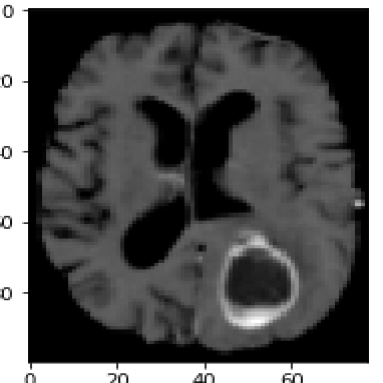

For the second medical example, we use image from the brain tumor segmentation (BRATS) challenge 2015 dataset; see https://www.smir.ch/BRATS/Start2015. The channels in this case consist of contrast-enhanced T1-weighted (T1c), T2 and fluid attenuated inversion recovery (FLAIR) images. Channels contain complementary information allowing accurate diagnosis and quantification of tumor growth. The top row in Fig. 7 shows the input images highlighting a different region of the tumor. Again, we exploit the information contained in different sequences by employing them as separate input channels. The proposed method is thus able to use this complementary information to delineate the different tissues and demonstrates solid results for this concrete example from medicine. The fact that the proposed energy functional can be applied directly to the given images, makes it particularly suitable for medical image segmentation.